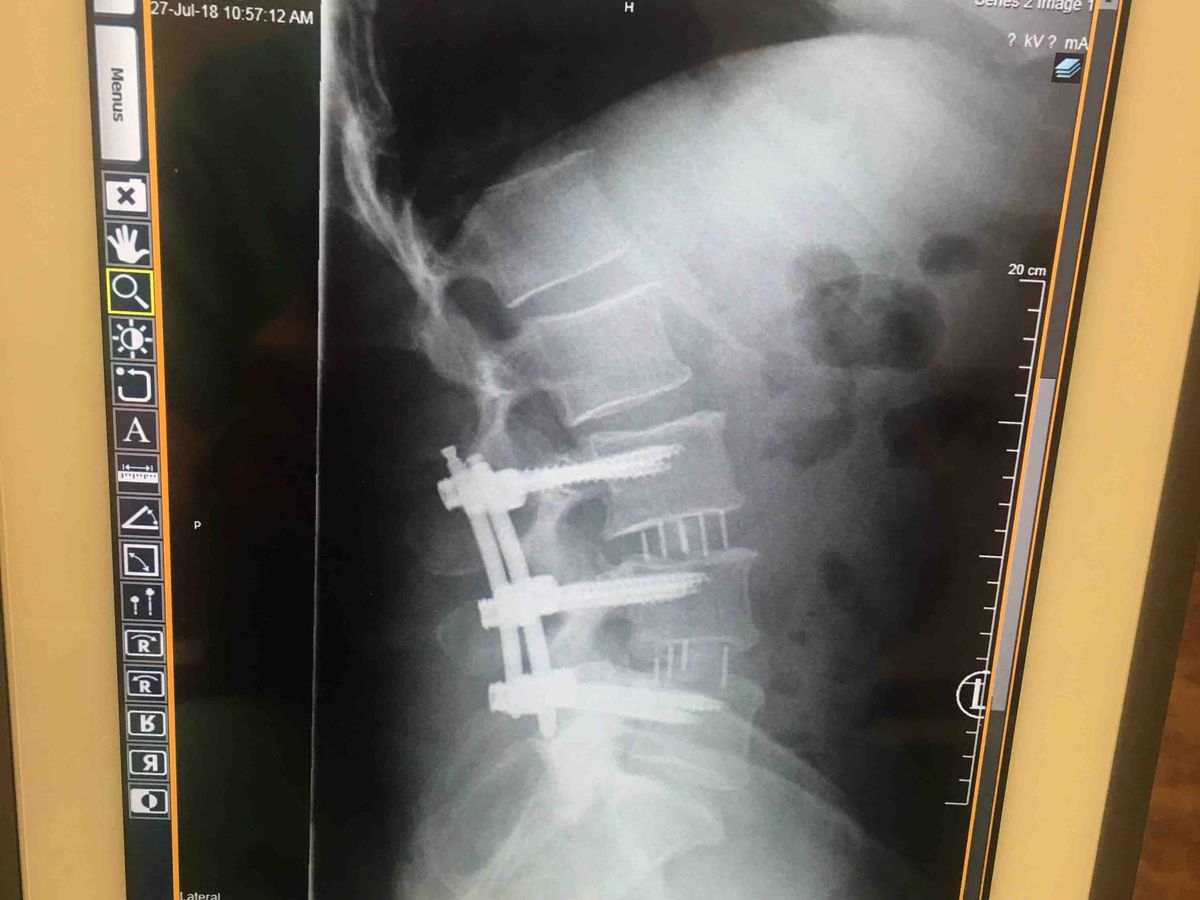

I went to the ER they performed an MRI and said I have 1 bulging disk another disk I smashed that is leaking fluid and on my sciatic nerve causing extreme pain in my right leg and hip. Went to the neurosurgeon and I have no other choice but surgery to take most or all of the pain away. And to be able to interact with my children And go back to work.

I had back surgery. Will be out of work for 4to5 months.